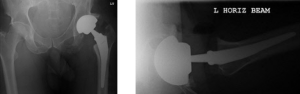

04-postop